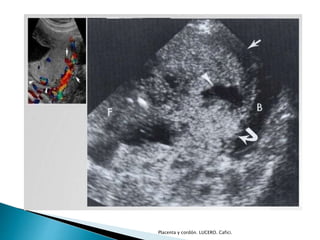

 Placenta con localización excéntrica del cordón

 Inserción marginal

◦ Cordón en el borde de la placenta

◦ Placenta en raqueta

 Inserción velamentosa

◦ Cordón a cierta distancia del borde placentario

◦ El cordón se inserta en las membranas

◦ Los vasos discurren entre el amnios y el corion

◦ No poseen protección de gelatina de Wharton

Placenta y cordón. LUCERO. Cafici.

 1% embarazo único, 9% embarazo gemelar

 Vasa previa

◦ Vasos de la inserción velamentosa atraviesan las membranas

fetales en el segmento inferior, por debajo de la presentación y

sobre el OCI

 Inserción del cordón en borde placentario

 Inserción en membranas ovulares

 Inserción en membranas ovulares y presencia

sobre OCI

 Utilización de doppler